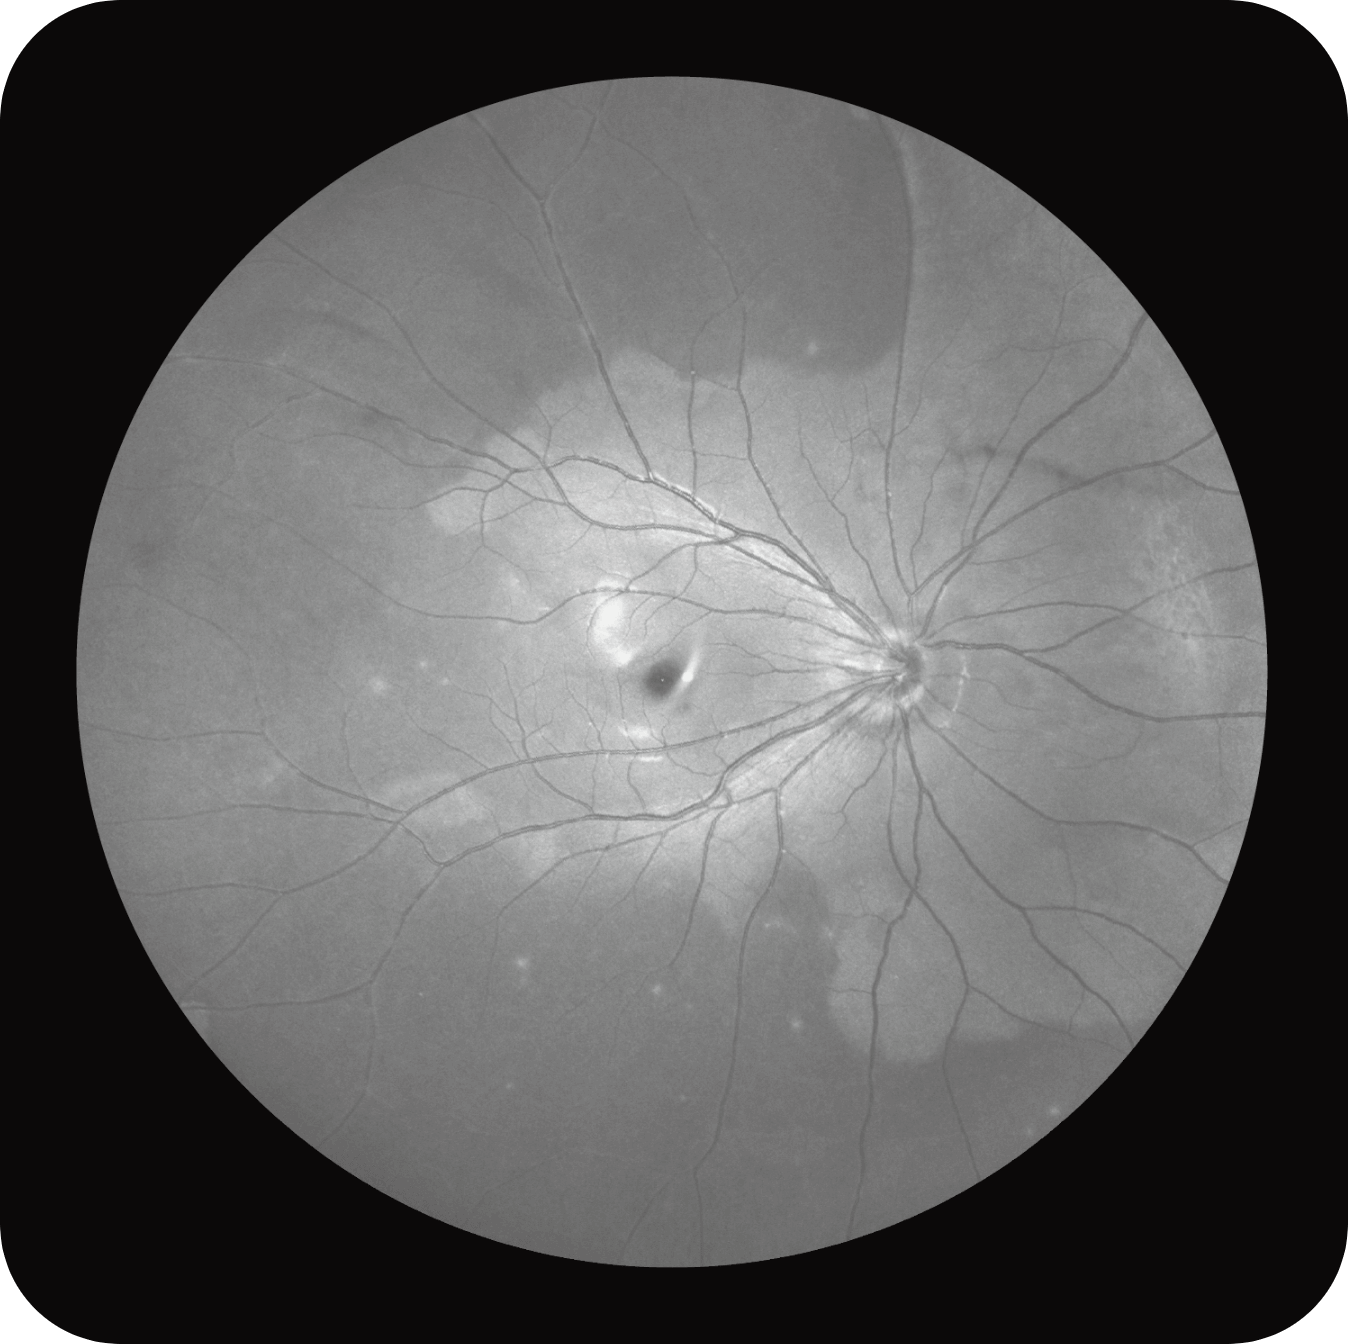

Olho Inteiro

Uma única varredura pode obter rapidamente imagens sincronizadas de imagens coloridas de campo ultralargo/FAF/FFA/ICGA e SS-OCT, alcançando sincronização em tempo real e alinhamento preciso de imagens planas e estruturais da retina, melhorando significativamente a eficiência da inspeção e otimizando o processo de diagnóstico e tratamento.” Uma única varredura pode obter rapidamente imagens sincronizadas de imagens coloridas de campo ultralargo/FAF/FFA/ICGA e SS-OCT, alcançando sincronização em tempo real e alinhamento preciso de imagens planas e estruturais da retina, melhorando significativamente a eficiência da inspeção e otimizando o processo de diagnóstico e tratamento.

Multi-Modalidade

Altamente integrado com tecnologias como SLO confocal e SS-OCT, ele combina imagens coloridas SLO de campo ultralargo, angiografia confocal a laser, autofluorescência e imagens tomográficas de segmento anterior e posterior ultraamplas e profundas em um único sistema.